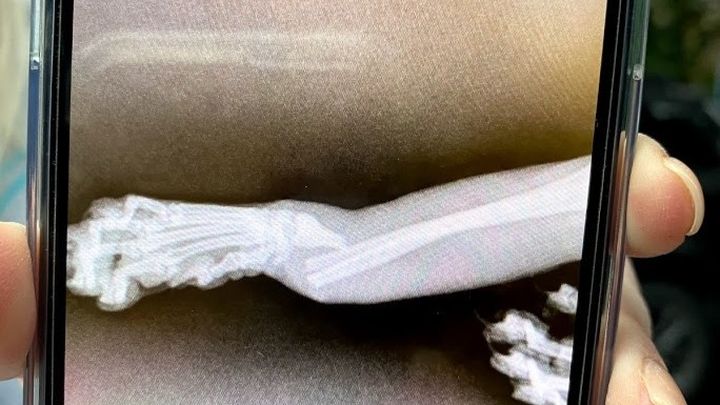

My two year old cat, Oka, accidentally fell from a balcony, and fractured his leg in the process. The surgery needed to help fix the issue, by putting a pin in the fractured area, costs a minimum of $2000, which I cannot afford by myself.

The most optimal time for me to have the funds needed for the surgery would be 1-2 weeks, as I can't bear to choose the option to amputate his leg. I want to save him. His specific ailment is "Fracture of Distal Ulna and Radius with Carpus Displace Cranially".